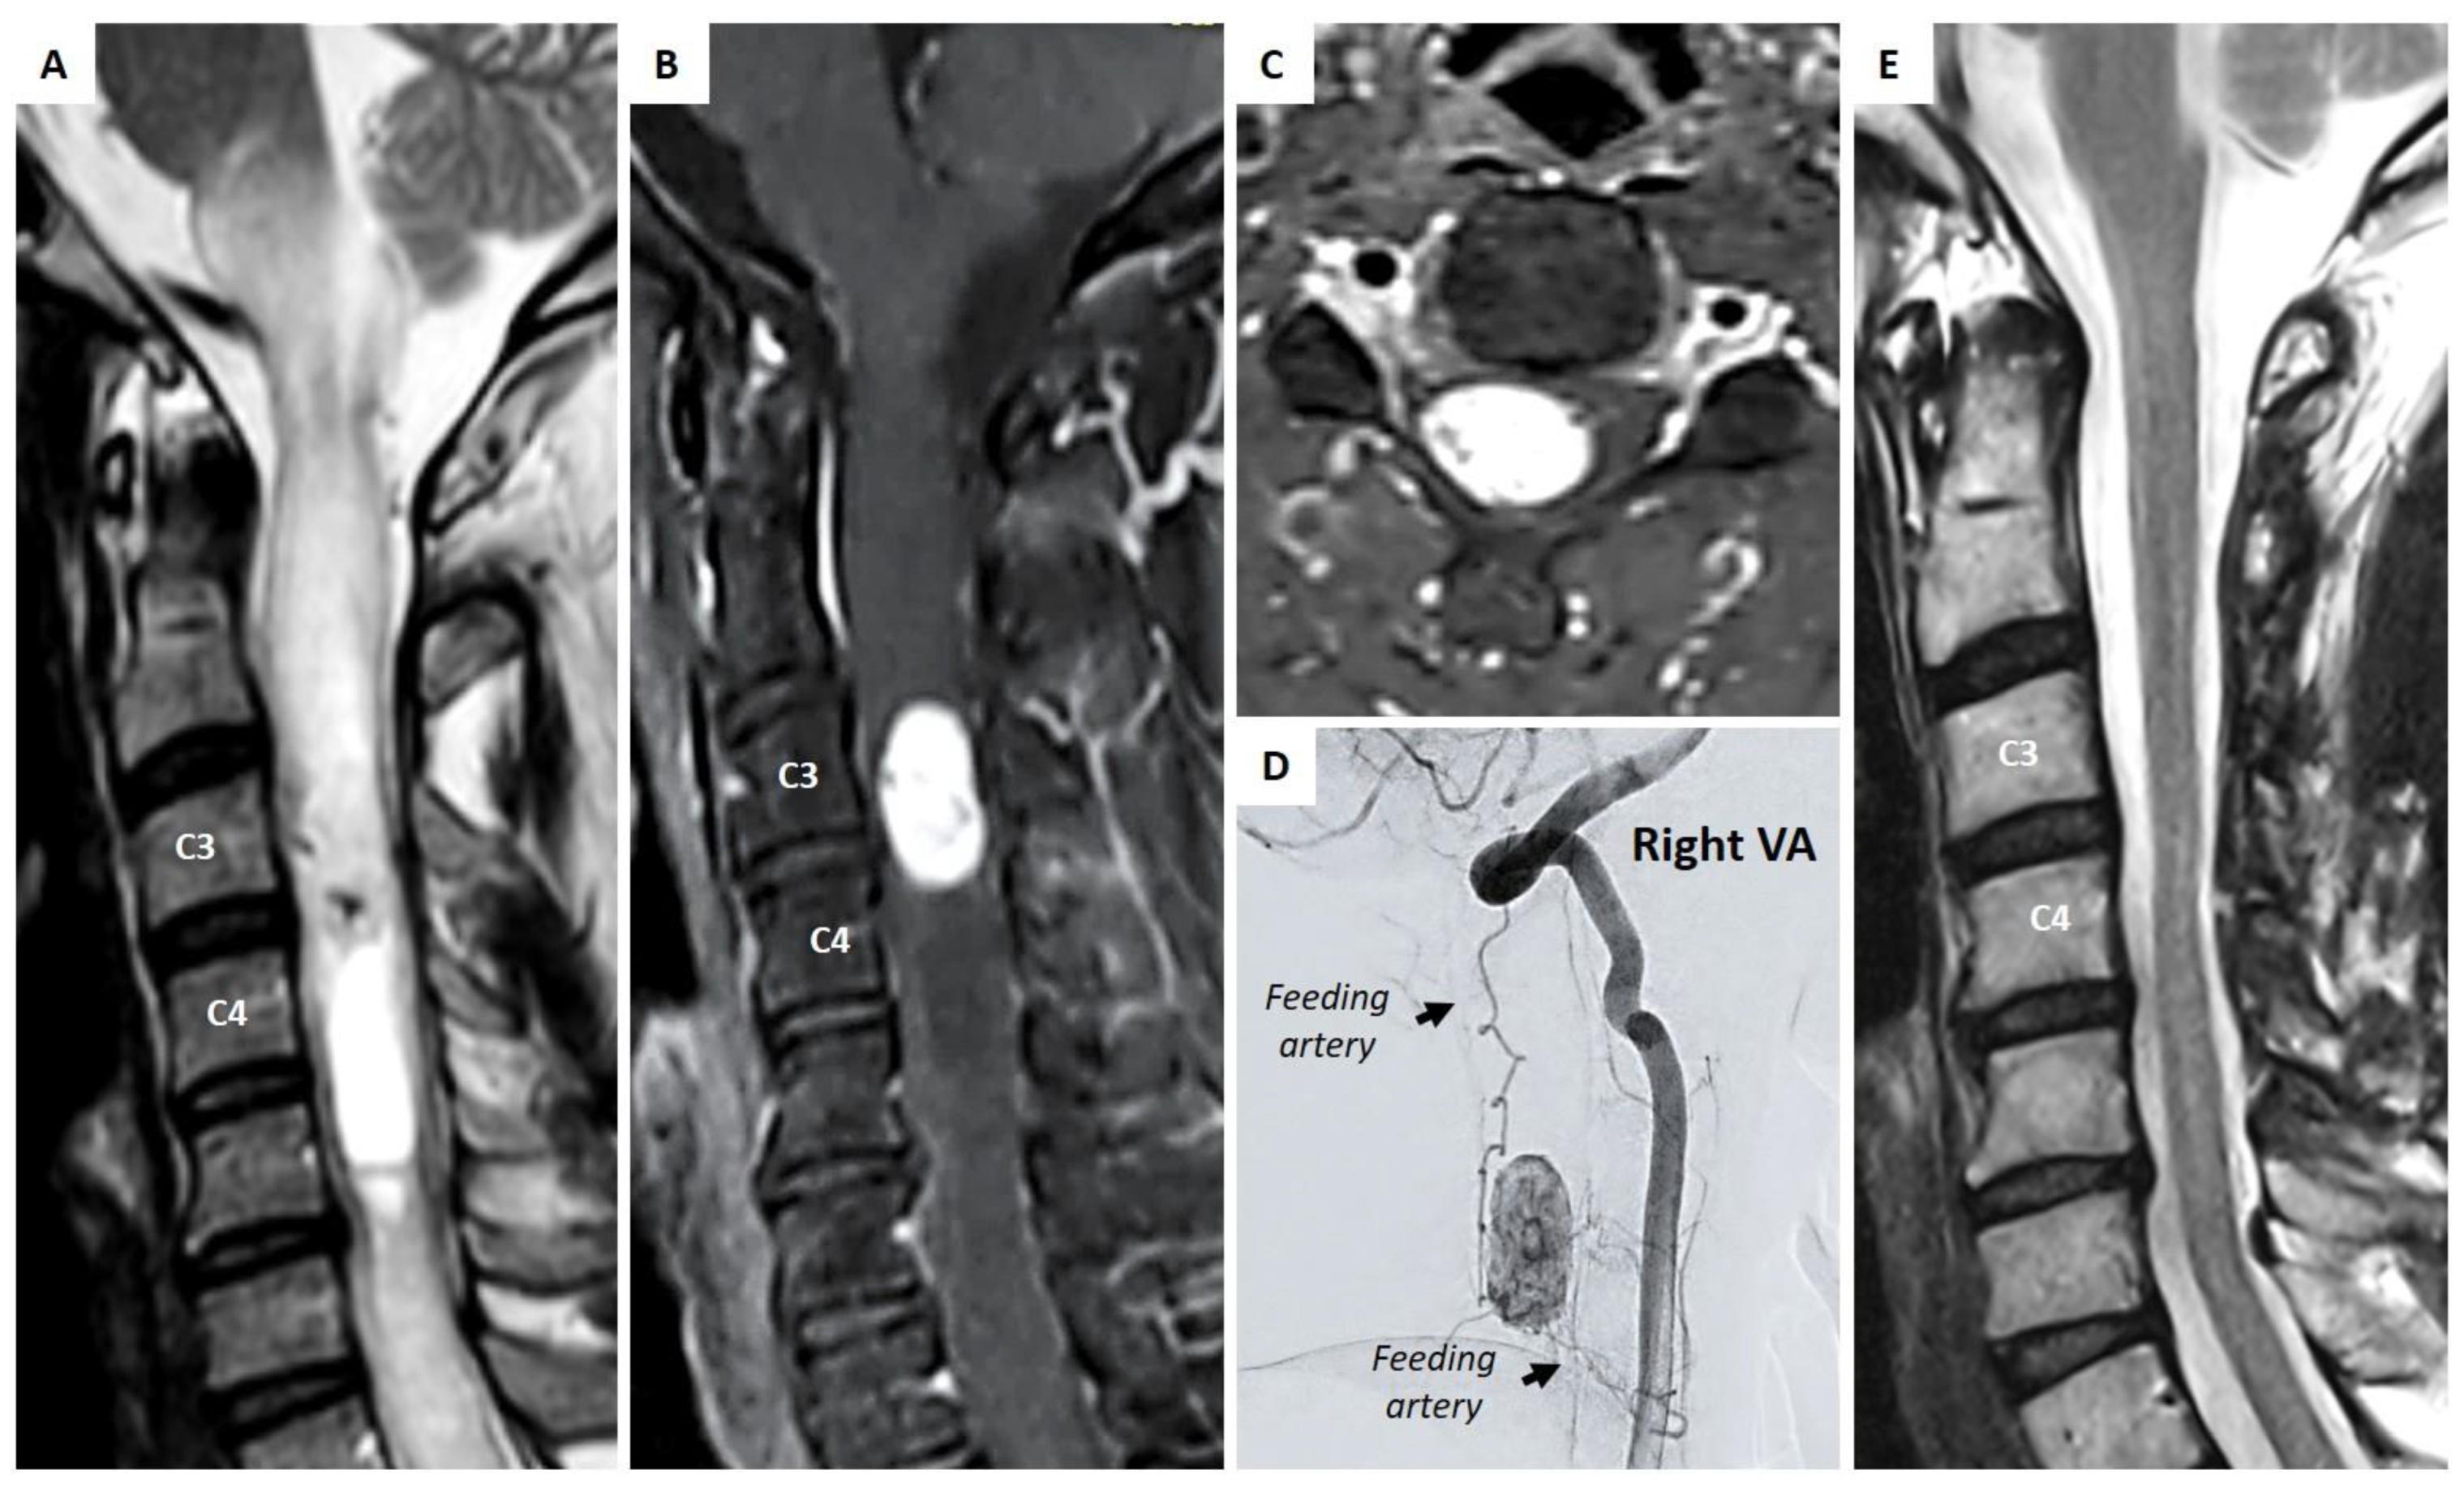

4.1. Illustrative Case